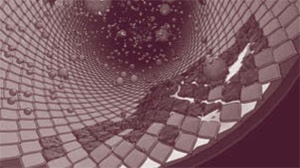

Рис. 3а

Рис. 3б

В ходе своих исследований доктор Эссельстин собрал новые доказательства того, что типичная западная диета, включающая переработанные масла, молочные и мясные продукты, разрушает клетки эндотелия, выстилающего изнутри стенки сосудов, и засоряет сосуды холестериновыми бляшками, которые препятствуют току крови. На рис. 3а показан кровеносный сосуд с бляшками, на рис. 3б – кровеносный сосуд человека, питающегося только продуктами растительного происхождения